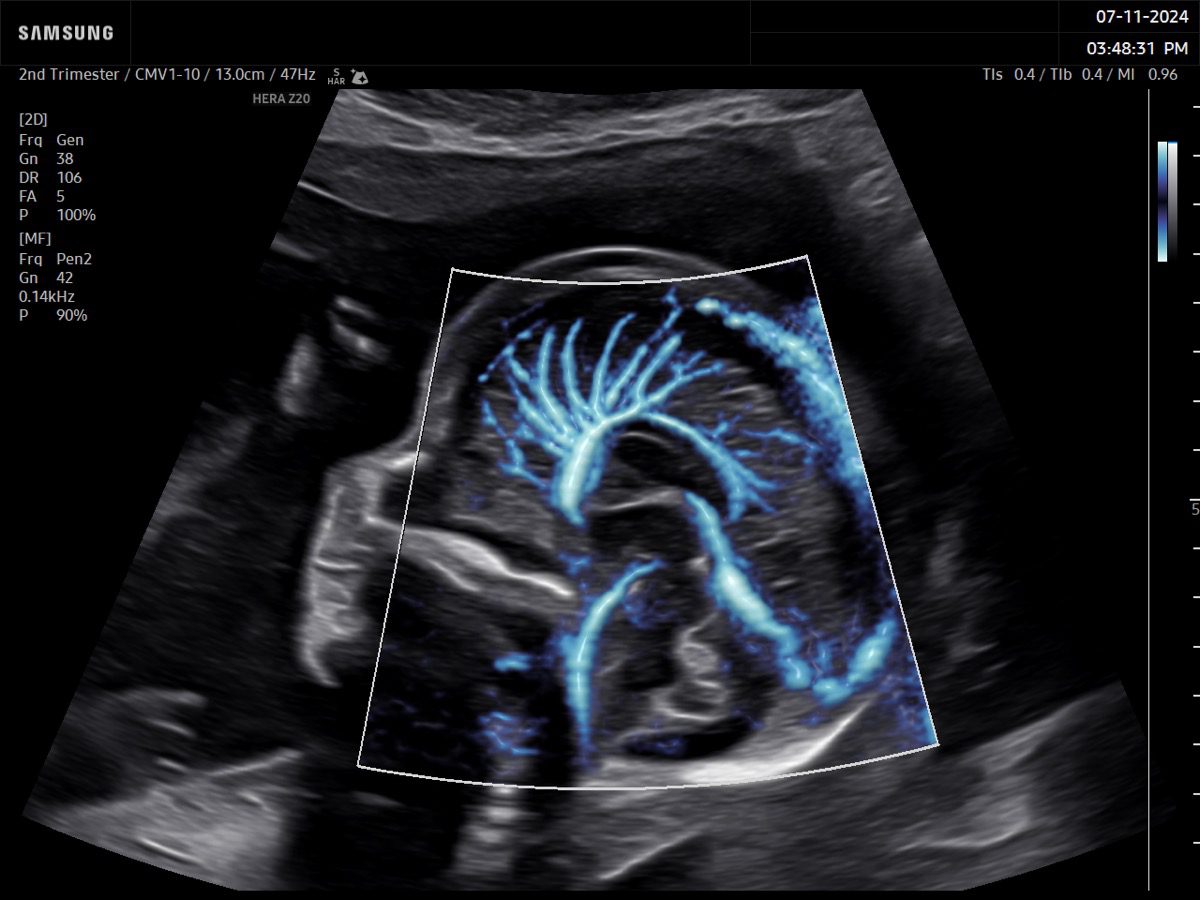

Comprehensive, advanced and expert MFM care for high-risk pregnancies

- Fetal anomalies